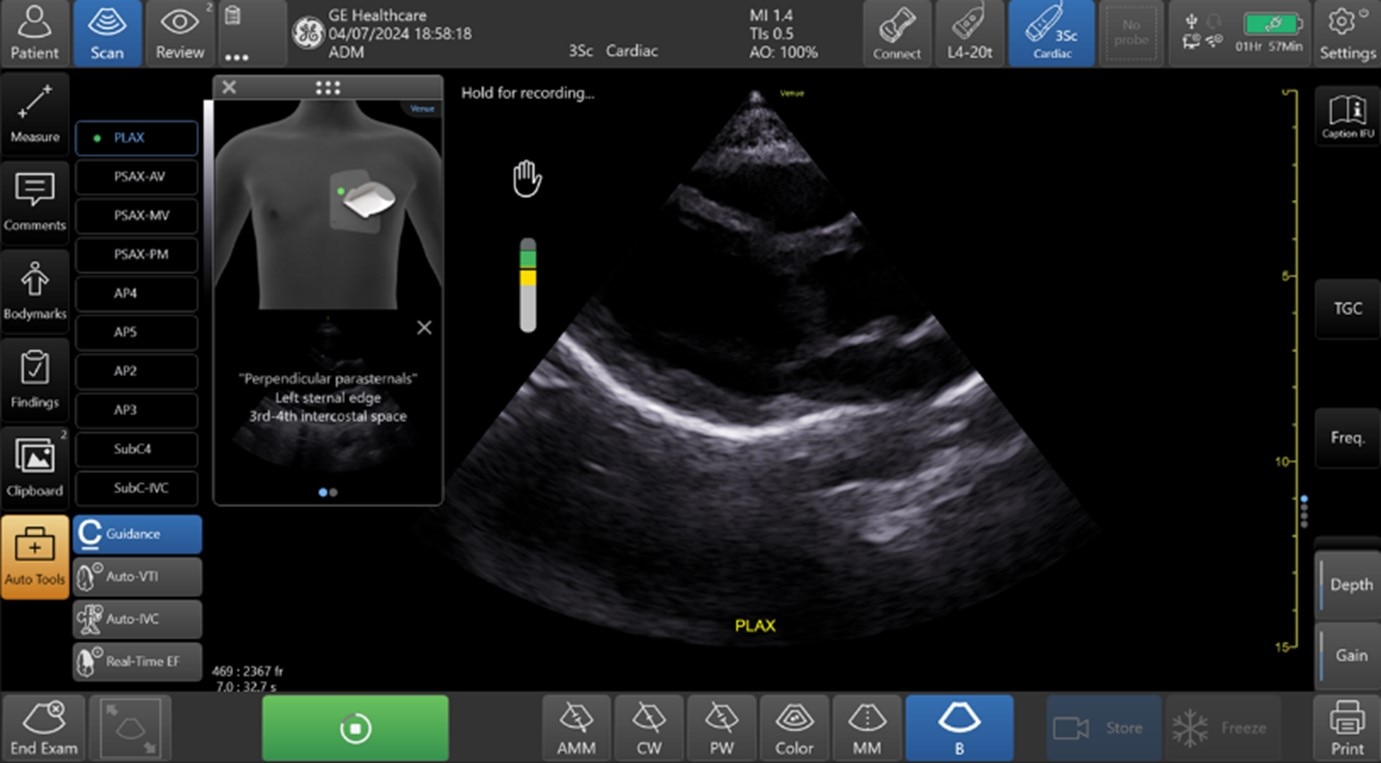

AIを用いて開発された「Caption Guidance」は、心エコー検査において、AIがプローブ位置を含む撮像の状態をリアルタイムに認識し操作者にガイダンスを行うことで、心エコーに慣れていない医療従事者でも高いクオリティの画像が安定して得られるよう、撮像自体をサポートする機能です。

「Caption Guidance」では、心エコー検査時に操作者に対してリアルタイムでプローブ走査をガイド表示し、プローブをあてる位置、角度、マークの方向など、より正確で高いクオリティの画像が得られるようにサポートします。これにより、複雑な心エコー検査をより簡便かつ正確に行えるようにサポートします。

また、最適なスキャン画像が得られているかの判断をアシストするインジケータ機能も備えており、スキャン画像が一定レベル以上のクオリティと認識された際に、操作者がプローブの位置を一定時間維持することで、自動的に画像を保存することも可能です。

※Caption Guidanceによる心エコー検査のリアルタイムガイド表示機能

中央左のインジケーター(Quality Meter)で画像クオリティを確認、その上部にはイラストとともに

「時計回りにゆっくりと回転」などリアルタイムに様々なガイダンスが表示されます。